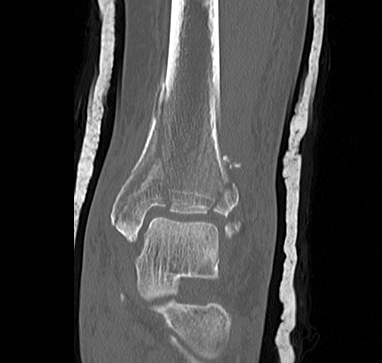

CT after external fixation application

CT scan

Commonly 3 fracture configurations

- medial malleolus

- posterolateral fragment / Volkmann

- anterolateral fragment / Chaput

Tibial plafond common fragmentsTibial plafond fragments